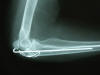

Fractura de olécranon con osteosíntesis.